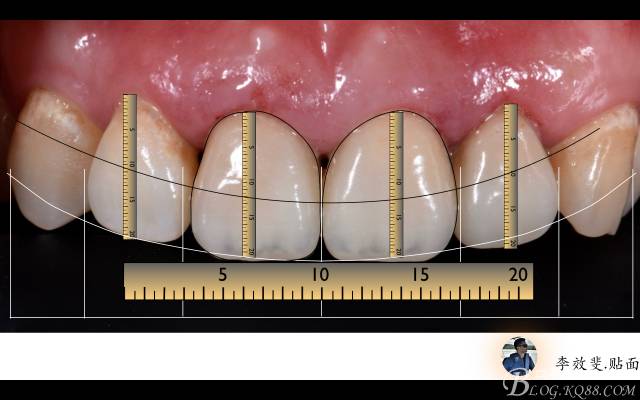

A:術(shù)后即刻微距拍攝分析,符合黃金比例,#11、#21之間,#11、#12之間牙齦乳頭有退縮,教會(huì)患者術(shù)后牙周護(hù)理方法,定期復(fù)查。